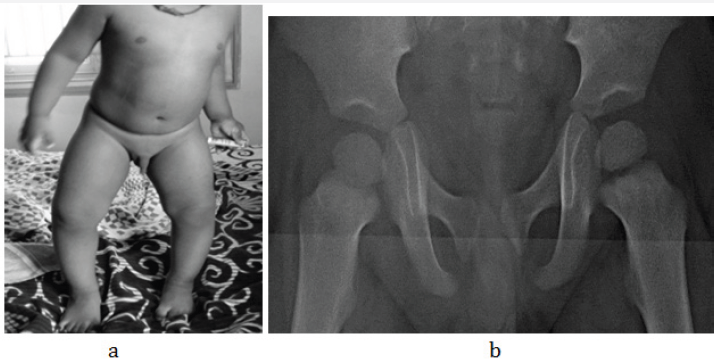

Figure 2 a & b: 2 M Rickets, a- clinical, b- radiograph of pelvis.

Figure 2 c& d: 1 1/2yrs, Rickets, a- hands, b- knees.

Figure 2 e & f: Rachitic rosary, a- chest, b- specimen of ribs.

In young children and adolescents, characteristic radiological appearances are noted on conventional films. These include osteoporosis, metaphyseal cupping and ground glass appearance of growing and weight bearing bones (Figure 2a-2d). Rachitic rosary deformity is common in the chest with cupping of the costochondral junctions (Figure 2e & 2f).